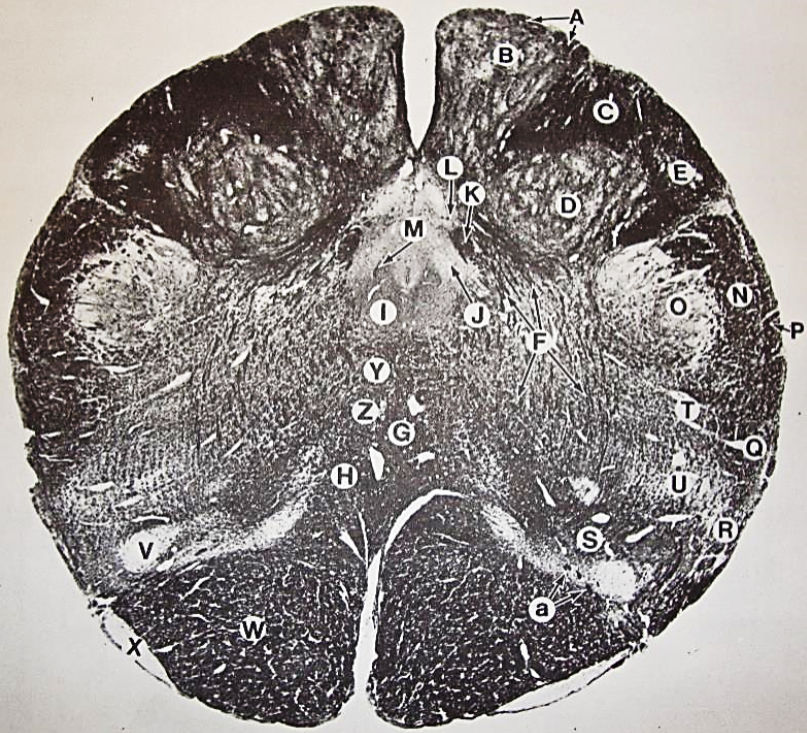

A

fasciculus gracilis

B

gracile nucleus

C

fasciculus cuneatus

D

cuneate nucleus

F

internal arcuate fibers

G

decussation of internal arcuate fibers

H

medial lemniscus

I

hypoglossal nucleus

J

dorsal motor nucleus vagus

K

solitary fasciculus

L

solitary nucleus

M

dorsal longitudinal fasciculus

N

spinal trigeminal tract

O

spinal trigeminal nucleus

P

posterior spinocerebellar tract

Q

anterior spinocerebellar tract

R

spinal lemniscus

S

lateral vestibulospinal tract

T

rubrospinal tract

U

lateral reticular nucleus

V

medial accessary olivary nucleus

W

pyramidal (corticospinal) tract

X

arcuate nucelus

Y

medial longitudinal fasciculus

Z

tectospinal tract

a

fascicles of hypoglossal nerve